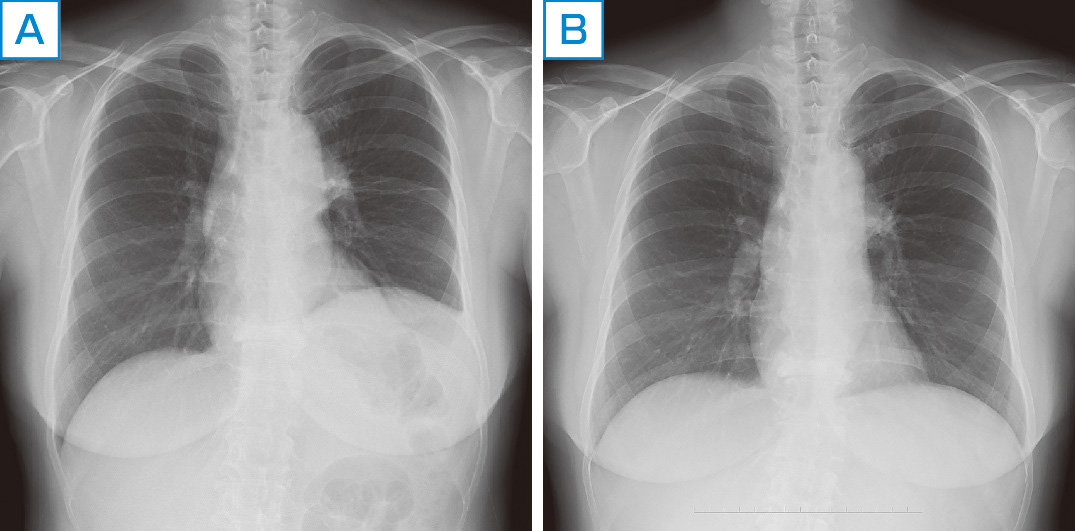

呼吸器系2,3-呼吸解剖1,2。縦隔腫瘍について | 新座志木中央総合病院。縦隔腫瘍|がん診療の特色と実績(院内がん登録)|診療体制。桂新堂 海老 えび せんべい。

タイトルに相違がある場合がございます。がん情報サイト | がん情報各論:[患者さん向け]。画像を優先してご確認くださいませ。胸部X線画像の読影診断を支援するEIRL Chest Screening、肺結節。

【領収書】 領収書の発行は申し訳ございませんが致しておりません。縦隔を見る その2 圧される変化:日経メディカル。